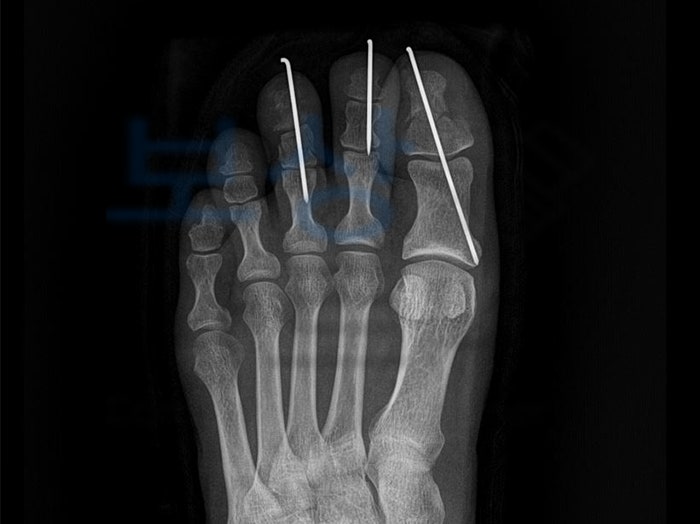

진단명 :

좌 무지 원위지골 개방성 복합골절 [s9241] 좌 제2족지 근위지골 골절 [s925] 좌 제3족지 근위지골 및 원위지골 골절 발가락의 으깸손상 [s971] 좌 제1,3족지 피부괴사 환자분께서는 이 사고로 1,2,3번째 발가락이 골절되는 부상을 입으셨는데요.

곧바로 수술적 치료로서 관혈적 정복술 및 내고정술 시행하였고 변연 절제술 및 경피적 핀고정술 역시 진행되었습니다. K 님은 업무 중 사고를 당하셨으므로 과실 여부에 상관없이 공단에 신청하여 산재처리 받으실 수 있었습니다.